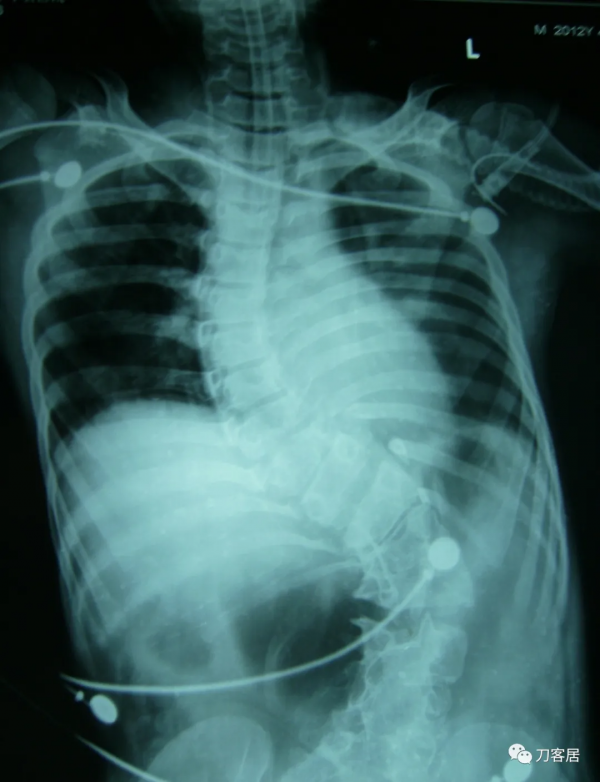

入院診斷:1.先天性脊柱側彎畸形;2.低位脊髓,脊髓栓系。入院後查血常規:WBC 4.30×109/L,RBC 4.83×1012/L,L 41.94%,N 46.54%,HB 134g/L,HCT 41.5%,PLT 295×109/L。尿常規示:PH 5.0,尿比重1.020。糞常規及潛血:正常。凝血四項:PT 12.7s,INR 1.02s,APTT 31.42s,TT 16.20s,FIB 2.27g/L。肝功:AST 32.3u/L,ALT 37.2,TBIL 11.3,IDBIL 7.6,DBIL 3.7,TP 72.3,ALB 45.2,GLO 27.1。腎功電解質:Urea 5.45mmol/L,Cr 51.6umol/L,UA 120.2umol/L,HCO 324.1mmol/L,K+ 3.95mmol/L,Na+ 137.9mmol/L,CI+ 99.1mmol/L,Ca+ 2.25mmol/L。心電圖:竇性心律,心電圖大致正常。胸部X線片:脊柱側彎,胸廓畸形,心肺膈未見異常。腰椎X線片:脊柱生理曲度消失,腰段脊柱向左側凸起,胸10為上端椎,腰5為下端椎,側凸85°,椎體旋轉II°至III°。胸段脊柱向右側突,以胸2為上端椎,胸10為下端椎,側凸90°,胸腰段輕度後凸畸形,Risser徵0級。胸11-腰1椎體分節不全,胸12及腰1及腰2-骶1附件融合。以腰1椎體為中心腰椎向右側凸出。腰1-2椎間隙增寬。診斷結果:先天性脊柱側彎畸形。MRI檢查:胸椎向右側彎曲,所見多胸椎體楔形變,多胸椎間隙不等寬:諸胸椎間盤未見明顯後凸;腰椎脊髓側彎,脊髓位置較低,約平腰3-4水平與硬囊關係緊密。診斷意見:脊柱側彎畸形,脊髓低位,脊髓栓系。心臟超聲檢查:EF55%,心內結構未見明顯異常,左室收縮功能正常,舒張期順應性好,彩色血流未見明顯異常。肺功能檢查:輕度混合型通氣障礙。VC 72%,FEV1 62%, MVV 46%。雙下肢神經電生理報告:DSEP:右側T8、L4,左側T12,雙側T10皮節-皮節P1波潛伏期延長。左側右側雙側皮節內踝-皮層波潛伏期延長。右側L2、5皮節-皮層P1波波幅較對側降低50%以上。視誘發電位CVEP示:雙眼視神經傳導大致正常。

13:00,血氣分析示:PH7.06, PCO2>115mmHg,PO2 83mmHg,Lac 1.4mmol/L,HCO3-測不出,BE測不出。急查胸片示:雙肺紋理模糊,右側肺門處可見片絮狀密度增高影,診斷:脊柱側彎畸形,右肺門片絮狀陰影考慮滲出性病變、炎症。再次給予5%的碳酸氫鈉60ml靜滴,並予以調整呼吸機呼吸頻率,延長吸氣時間,過度通氣等。

患者術前